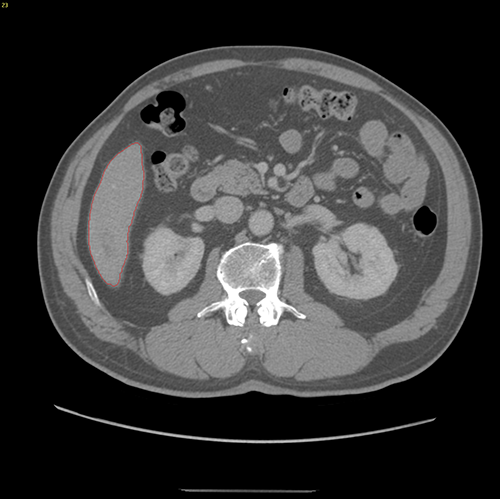

S6肝癌-腹腔镜S6切除